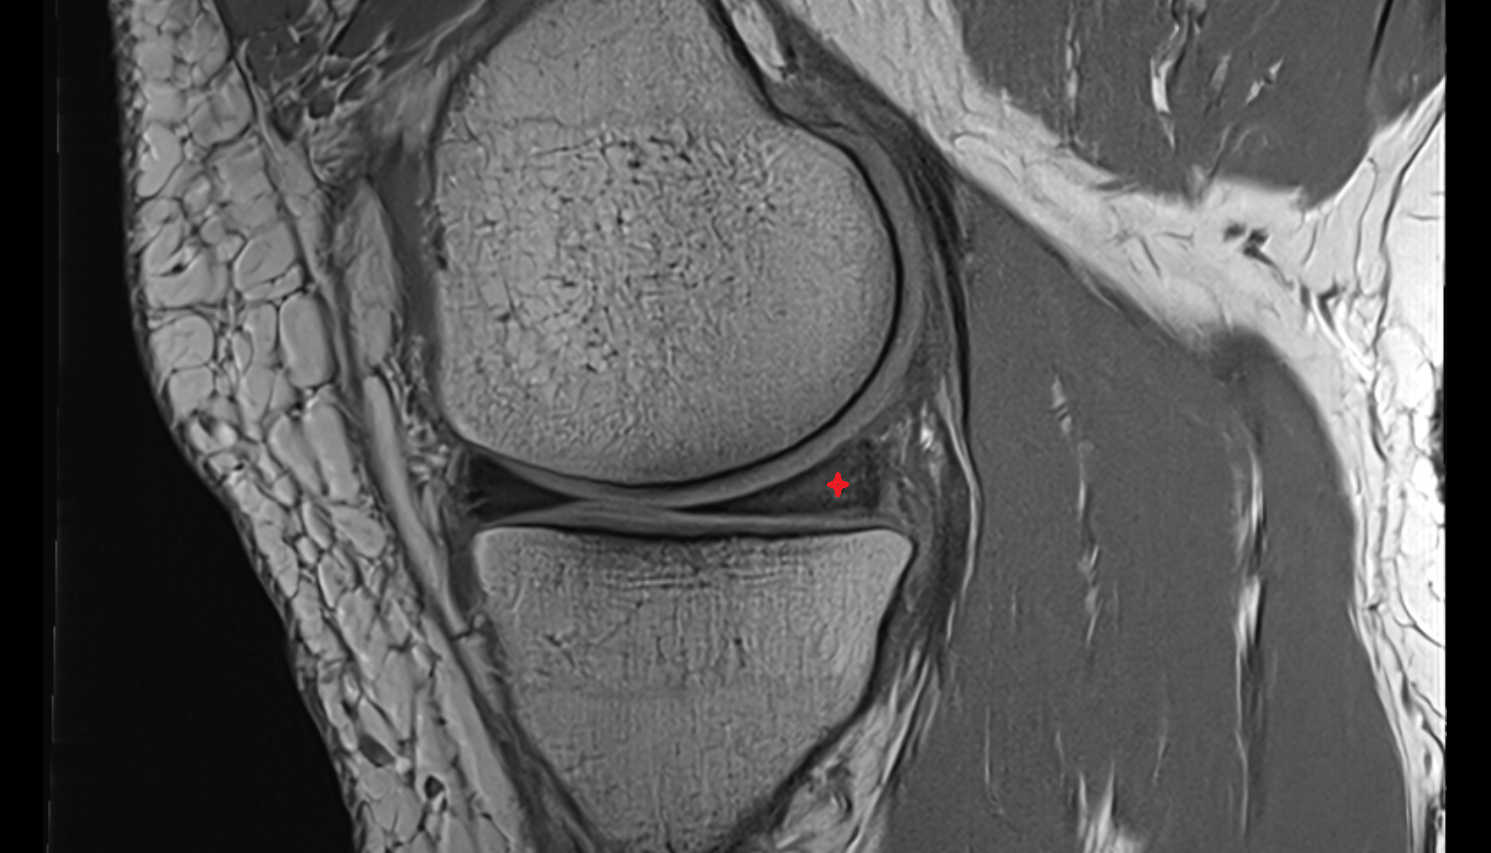

- Anterior cruciate ligament

- Posterior cruciate ligament

- Medial meniscus

- Lateral meniscus

- Knee Joint